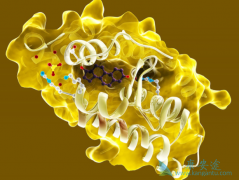

奥拉帕尼( olaparib )是一种称为PARP抑制剂的药物。PARP是一种蛋白质,可帮助受损细胞修复其DNA。像奥拉帕尼这样的药物可以阻止PARP的修复作用。具有错误BRCA基因的癌细胞依赖PARP来保持其DNA健康。当奥拉帕尼阻止PARP修复DNA损伤时,癌细胞就会死亡。奥 ...

BRAF是人类最重要的原癌基因之一,BRAF绝大部分发生BRAF V600E突变,从而导致了下游MEK-ERK信号通路的持续激活。V600E发生突变对肿瘤的生长增殖和侵袭转移至关重要。威罗菲尼( Vemurafenib )能够选择性地抑制BRAF V600E激酶,进而阻断了肿瘤细胞的下游通 ...